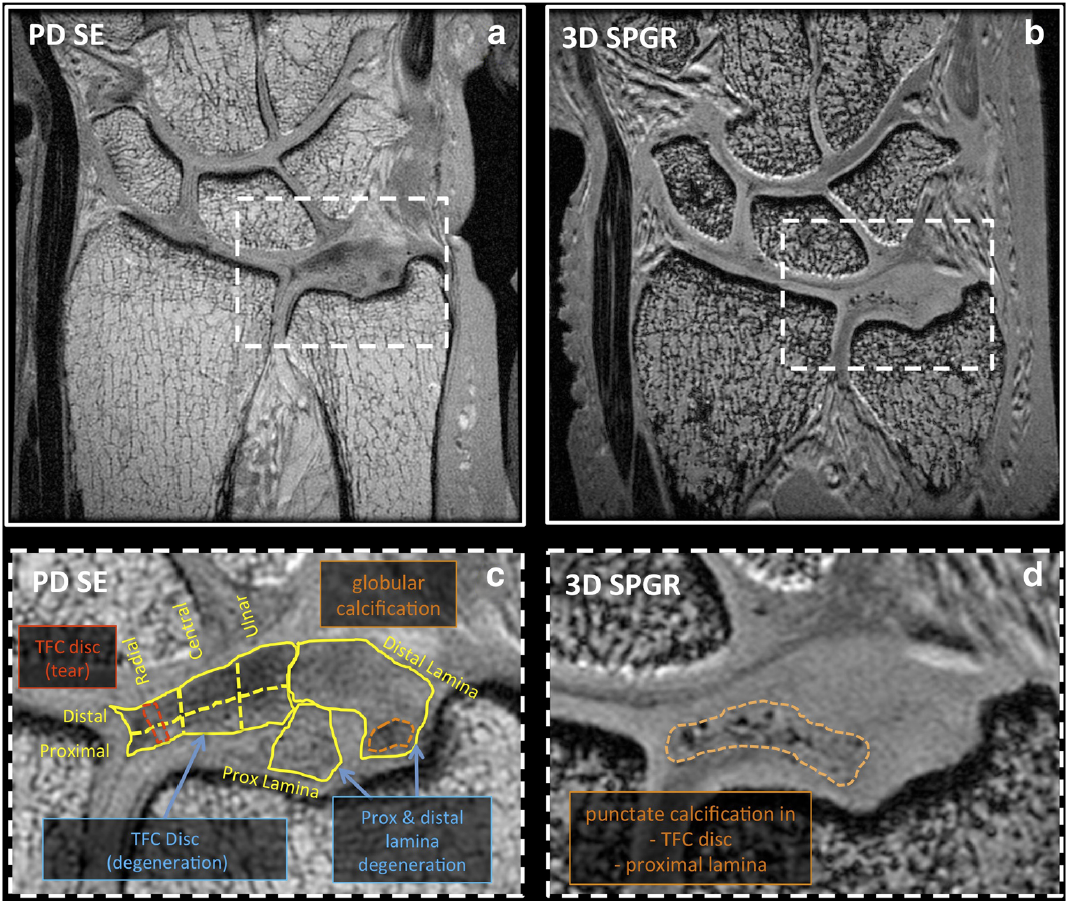

On morphologic PD SE images, TFC disc pathology

included degeneration and tears, while that of the laminae

included degeneration, degeneration with superimposed tear,

mucinous transformation, and globular calcification. Punctate

calcifications were highly visible on 3D SPGR images and

found only in pathologic regions. Disc pathology occurred

more frequently in proximal regions of the disc than distal

regions.